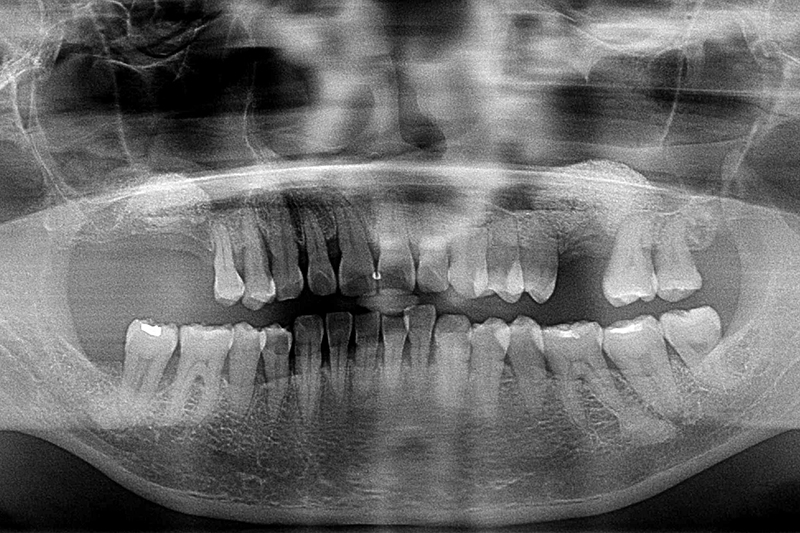

缺牙多顆-全口X光攝影

案例二

術前

術後